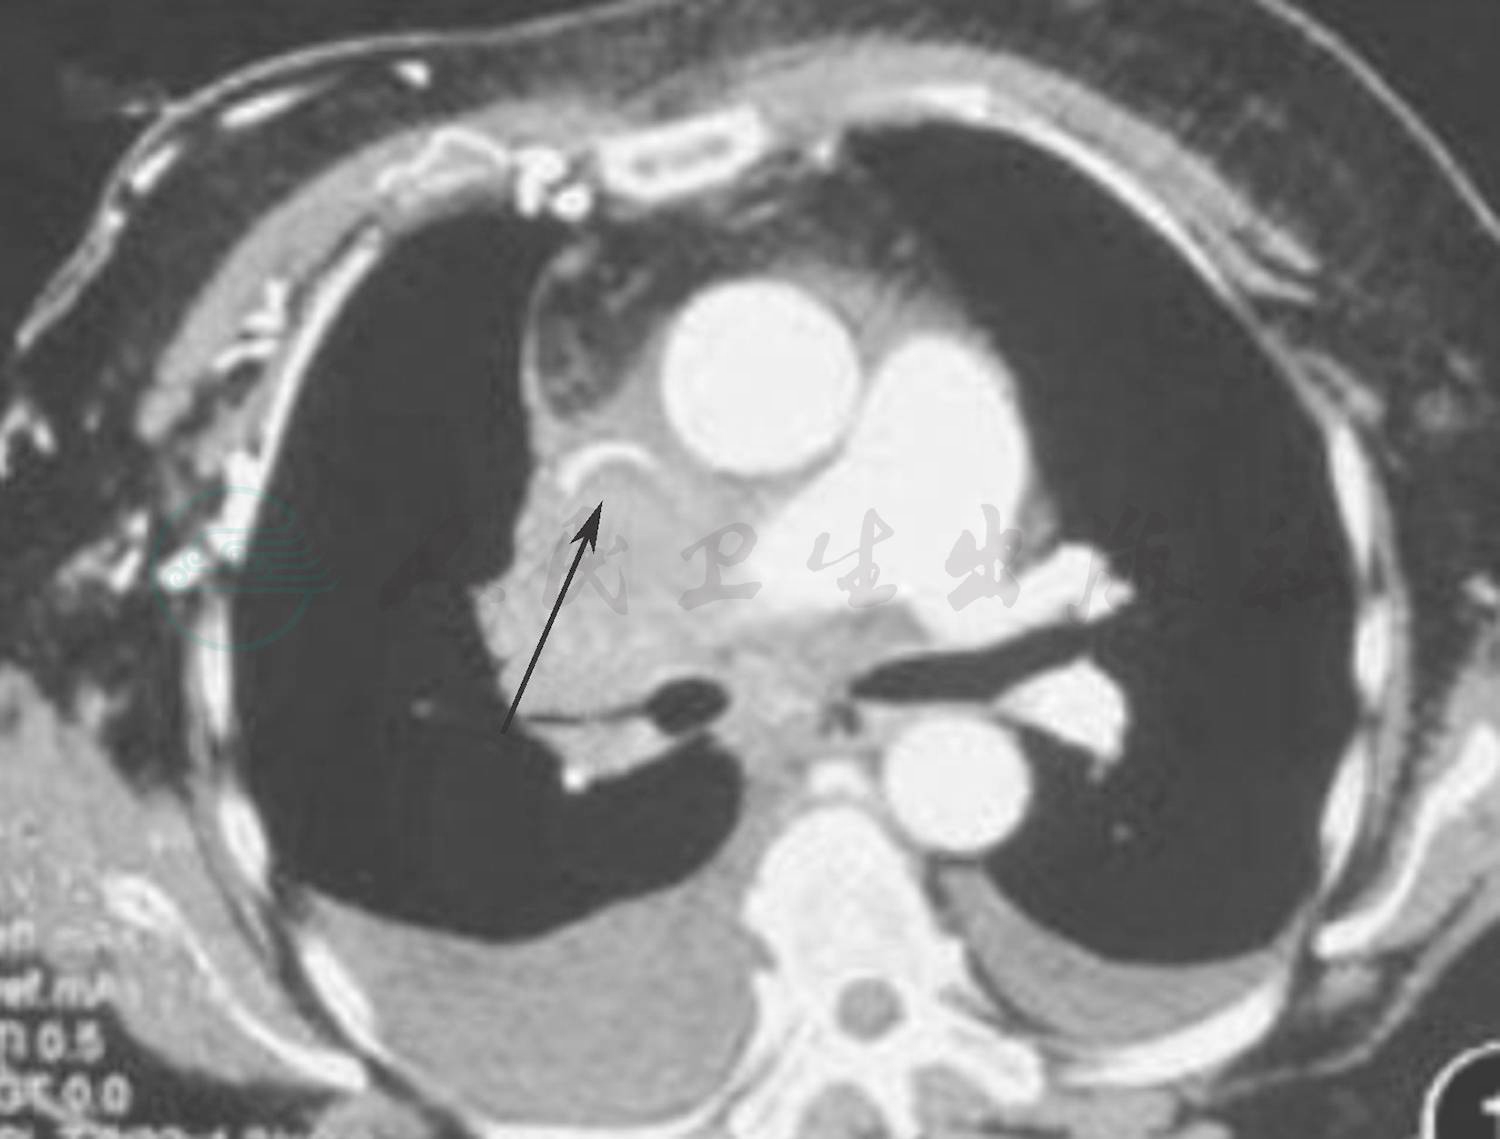

血常规、肝肾功能试验、血脂、胰淀粉酶和脂肪酶、叶酸和维生素B12、甲状腺功能试验,以及血清甲状腺抗体均于正常值范围。动脉血气分析:经皮动脉血氧饱和度(SpO2)95%、动脉血氧分压(PaO2)67.80mmHg、二氧化碳分压(PaCO2)41mmHg,碳酸氢根 24.90mmol/L,pH值7.40。纤维蛋白原5.57g/L(1.80~3.50g/L)、D-二聚体0.98mg/L(0~55mg/L),超敏C反应蛋白(hsCRP)14.18mg/L(0~3mg/L),红细胞沉降率(ESR)67mm/h。风湿免疫学检测:狼疮抗凝物、抗核抗体(ANA)19项、抗可提取性核抗原(ENA)抗体、抗心磷脂抗体(ACA)、β2-糖蛋白1(β2-GP1)抗体、抗中性粒细胞胞质抗体(ANCA)均呈阴性反应。肿瘤标志物:糖链抗原(CA)24227.50U/ml(参考值范围0~20U/ml)、CA19-9 47.10U/ml(参考值范围10~34U/ml);血清蛋白电泳呈阴性。尿常规提示泌尿系统感染。腰椎穿刺脑脊液检查外观澄清、透明,压力>330mmH2O,白细胞计数1×109/L,单核细胞计数1×106/L,蛋白定量、葡萄糖、氯化物均于正常值范围;抗单纯疱疹病毒、巨细胞病毒抗体gM,以及细菌培养、抗酸染色、墨汁染色呈阴性;细胞学检测未见异常。血清和脑脊液抗电压门控钾离子通道(VGKC)抗体、N-甲基-D-天冬氨酸受体(NMDAR)抗体、神经节苷脂GM1抗体、抗Hu、Yo、Ri抗体呈阴性。头部常规MRI和磁敏感加权成像(SWI)未见明显异常;MRV检查下矢状窦未显影,其余无异常。甲状腺和颈部淋巴结超声显示右侧锁骨上窝淋巴结异常增大(第Ⅳ区即颈内静脉淋巴结下组),并可见双侧颈部淋巴结。乳腺超声可见双侧腋下淋巴结,左侧淋巴结部分回声减低。胸腹盆腔CT增强扫描显示纵隔多发性占位性病变,考虑恶性病变;上腔静脉综合征;双侧胸腔积液,双肺受压膨胀不完全;双侧胸膜增厚;心包积液(图1)。全身PET/CT扫描可见右上纵隔代谢异常增高的不规则肿块,堵塞右主支气管和右上叶尖段支气管,呈恶性改变,考虑中央型肺癌伴邻近肺门和纵隔淋巴结转移、右侧锁骨下淋巴结转移;第Ⅳ肝段代谢轻度增高,考虑肿瘤转移;心包积液、双侧胸腔积液;右肺膨胀不完全(图2)。临床诊断:纵隔多发性占位性病变,考虑恶性病变可能;上腔静脉受压;颅内压增高;副肿瘤综合征。入院后予甘露醇125ml和甘油果糖250ml(1次/12h)静脉滴注以降低颅内压,同时予鼻导管吸氧、肠内营养等对症治疗。

图2 患者全身PET/CT扫描

显示纵隔占位性病变(箭头所示)伴淋巴结和肝脏转移